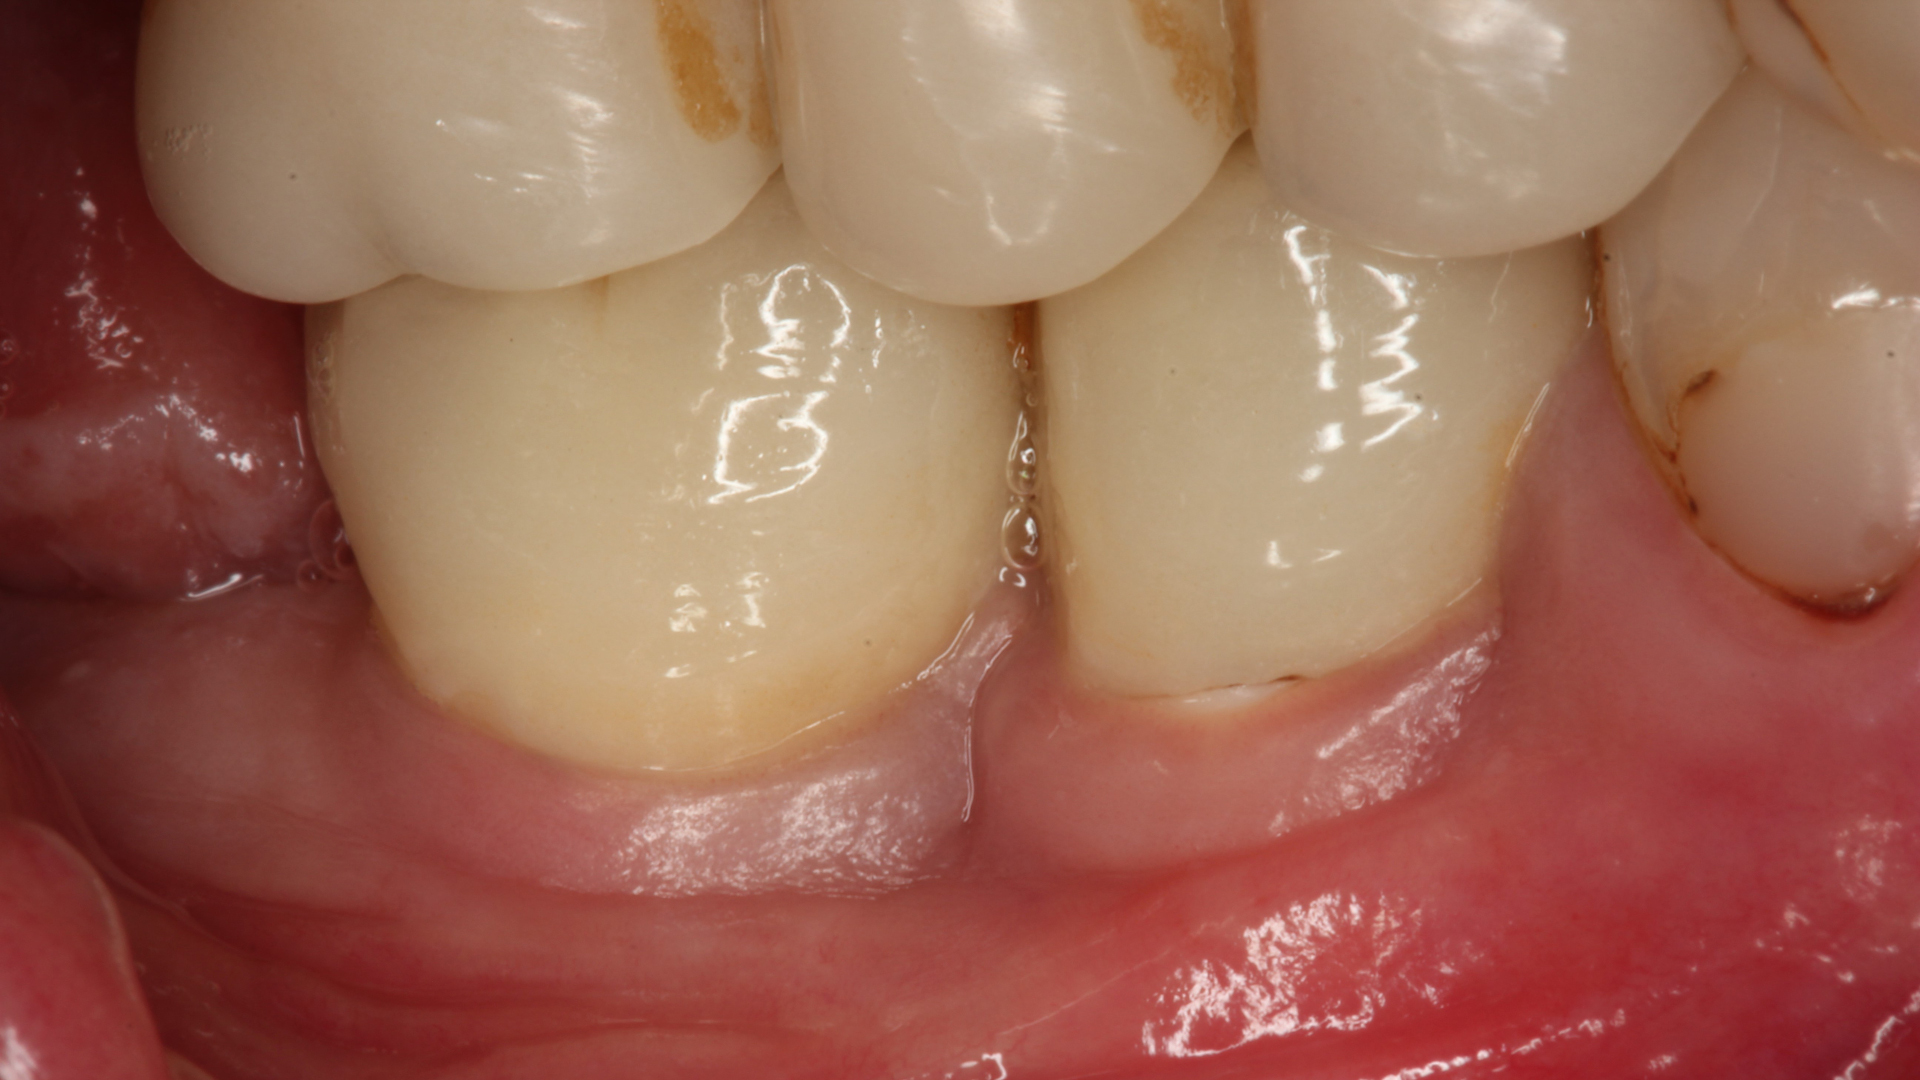

The study included patients with challenging conditions for implant treatment, such as Down’s syndrome or cancer, or those on medications like antihypertensives and immunosuppressants. (Image: Karapataki et al. 2023)

In the study, Dr Karapataki aimed to validate her own clinical experiences by including patients with challenging conditions for implant treatment, such as Down’s syndrome or cancer, or those on medications like antihypertensives and immunosuppressants, as well as patients with periodontitis or thin gingival biotypes and those who smoked heavily. Remarkably, even after 12 years, these patients maintained stable and healthy tissue levels around their implants. “If an implant system performs well in the demanding daily clinical environment, where patients with general health conditions and various risk factors are common, then we can hope for more implant treatments without peri-implantitis in day-to-day implant practice,” Dr Karapataki said.